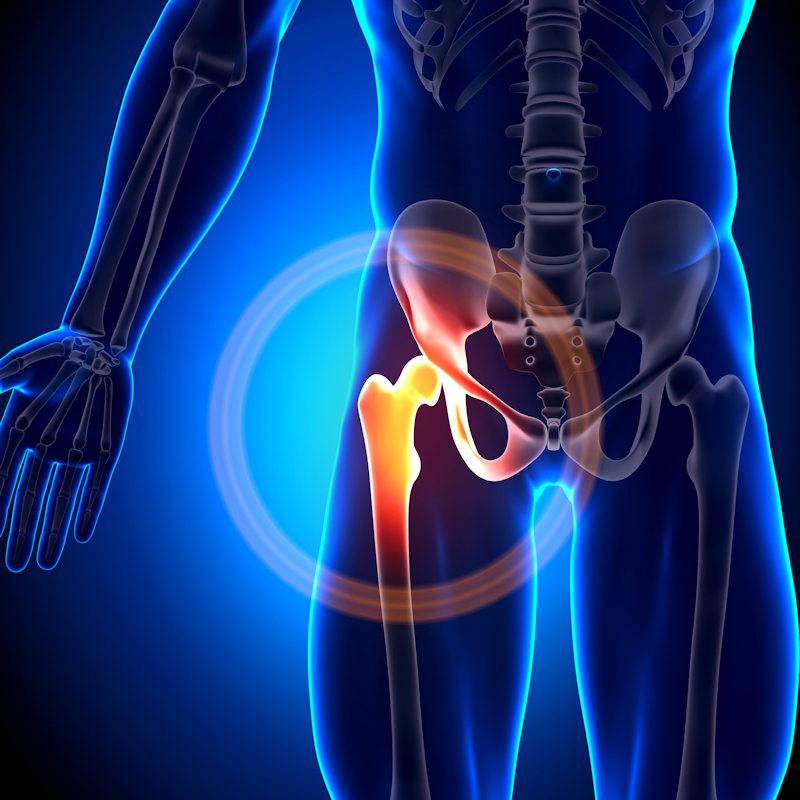

Nearly 80% of early breast cancers in postmenopausal women are hormone receptor (HR)-positive, with five-year adjuvant treatment with aromatase inhibitors the gold standard therapy for these patients, the authors explained. The treatment decreases bone mineral density, however, which increases the risk of bone fracture, and thus osteoporosis medications such as denosumab are also prescribed.

Out of 237 patients (median age, 61 years old), 17 (4.4%) had VF progression, according to the results. A multivariable analysis showed that high percentages (above the median) of fat body mass (odds ratio [OR] = 5.41; P = .01) and high FRAX scores (OR, 3.95; P = .04) in these women were independent variables associated with VF progression.

“These data contrast with those reported for postmenopausal women, in which obesity often plays a protective role,” the authors noted.

Moreover, the study raises doubt about current bone health recommendations for these patients from the American Society of Clinical Oncology and European Society for Medical Oncology, which state that high body mass index is a low risk factor, they added.